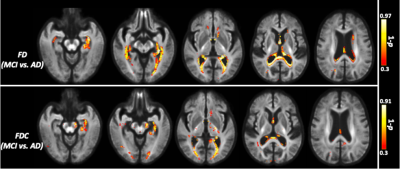

The whole-brain FBA showed significant reduction in FD in individuals with AD compared to MCI, in regions including splenium of corpus collosum, fornix, and the left uncinate fasciculus. Furthermore, AD showed significant reduction in FD in the left uncinate fasciculus compared to controls. Figure 2 shows WM tracts where significant (FWE corrected p <0.05) reductions in FD were observed.We observed subtle reduction in FD and FDC metrics (although the differences were not statistically significant after FWE corrections) in regions including corpus callosum (bilaterally), forceps majors (bilaterally), and uncinate fasciculus in AD compared to MCI. The reduction in FD was more pronounced compared to the reduction in FDC (Figure 3).Furthermore, FD and FDC were observed to be reduced (although not statistically significant after FWE correction) in regions including uncinate and the arcuate fasciculus (bilaterally) in AD relative to controls (Figure 4). We did not observe notable difference in FC in any groups. There were no reductions in FBA measures in MCI relative to controls.

Figure 3: Fibre tract-specific reductions in AD compared to MCI from whole-brain FBA. The white matter regions showing subtle (statistically not significant after FWE correction) to significant reductions in FD, and FDC are superimposed onto the population template.

Figure 4: Fibre tract-specific reductions in AD compared to controls from whole-brain FBA. The white matter regions showing subtle (statistically not significant after FWE correction) to significant reductions in FD, and FDC are superimposed onto the population template.